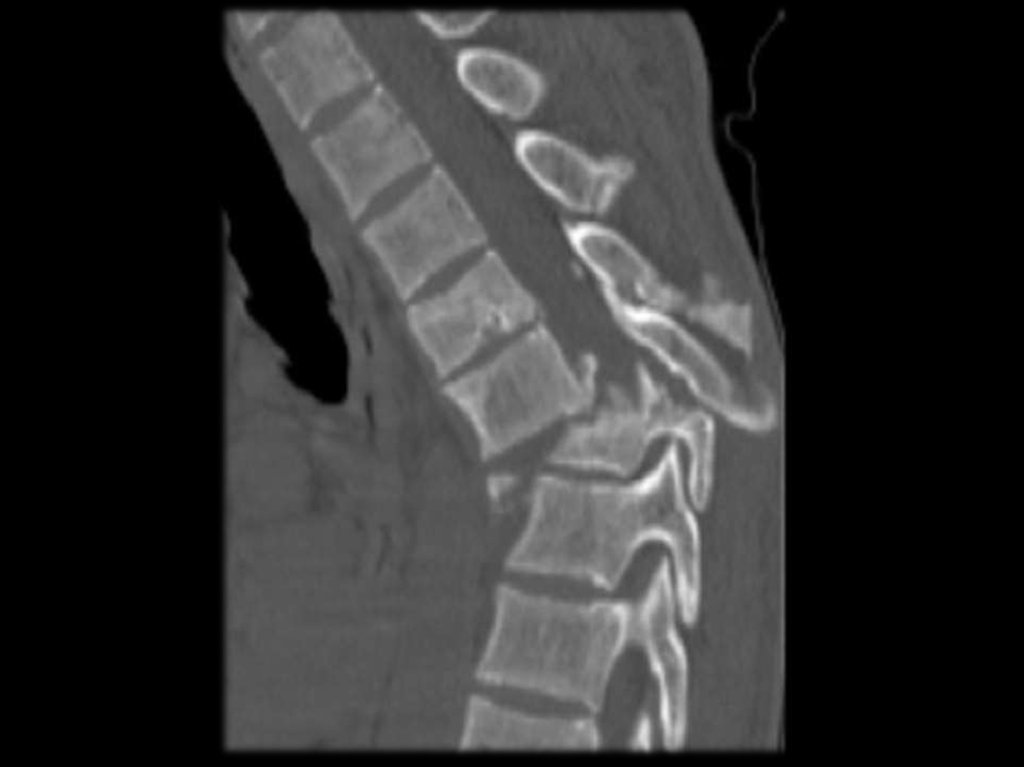

15. Локализация переломов

Позвонки

Шейка бедра

Предплечье

R-признаки при ОП (R-графия позвонков в

боковой проекции), потеря костной массы

при этом составляет 20 – 30%.

разряжение губчатой кости;

уменьшение количества трабекул на

единицу плотности кости;

повышенная прозрачность тел позвонков;

видны вертикальные трабекулы;

“рамочная” структура

тел

позвонков

(истончение и резкая подчёркнутость

контуров кортикального слоя кости при

разряжении

плотности

кости

тела

позвонка);

деформация тел позвонков

Виды деформации тел позвонков:

передняя клиновидная;

задняя клиновидная;

двояковогнутая деформация (по типу

“рыбьих”);

компрессионная деформация;

сочетанная.